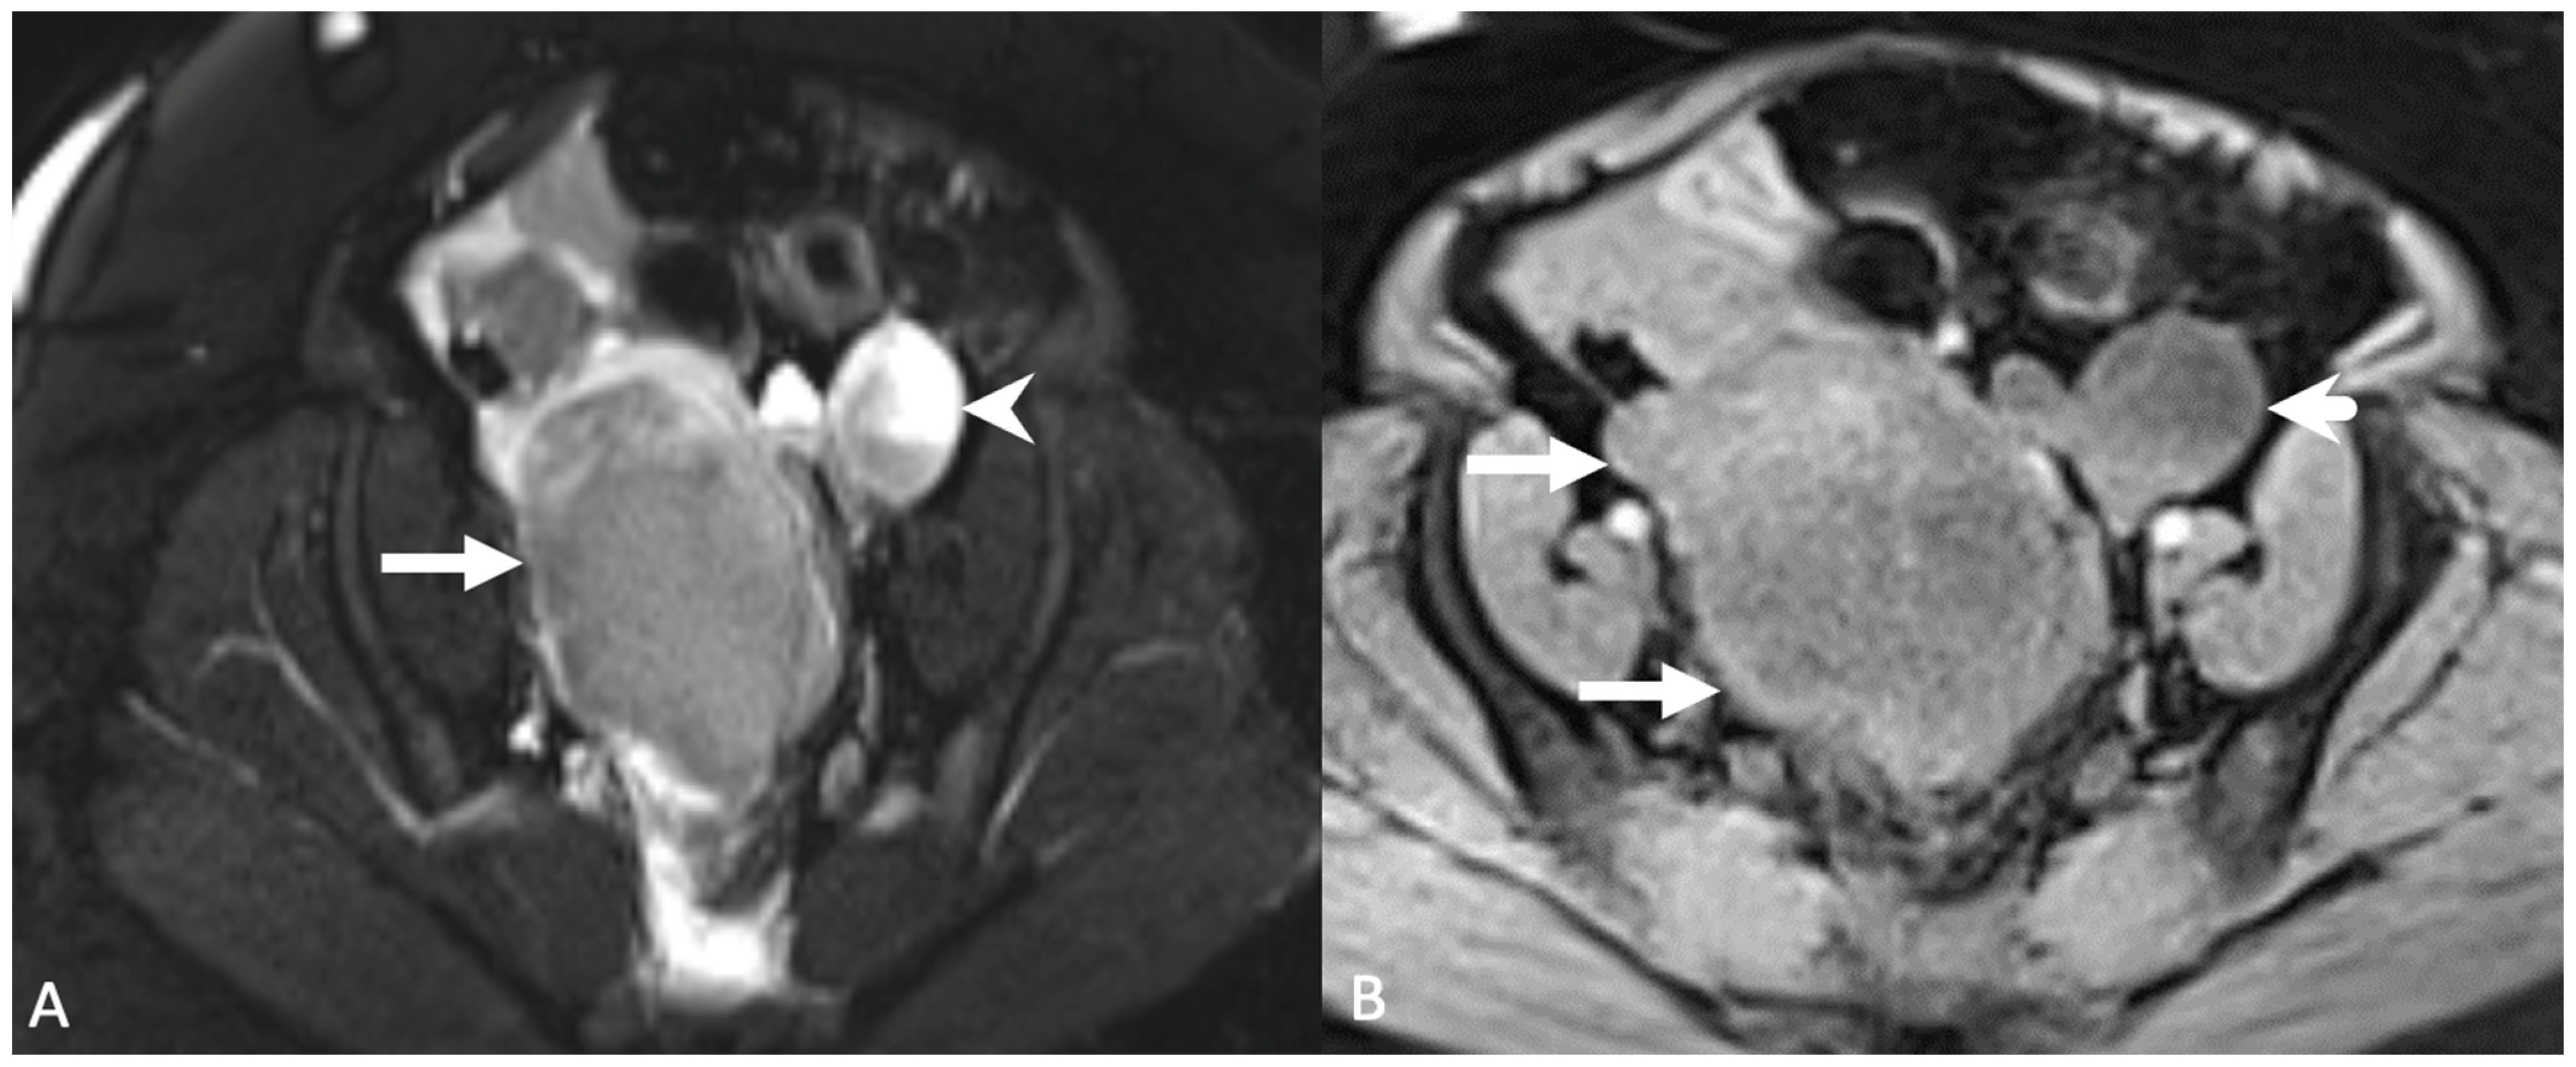

4. Imaging

5.2.1. Uterine Vasculature

5.2.2. Leiomyoma